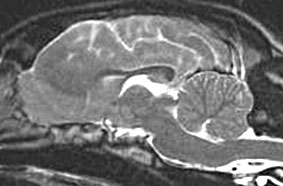

This Concept Map, created with IHMC CmapTools, has information related to: Nervous System Tissues and Cells, Microscopic Anatomy studied by Microscopy, Cerebral Aquaduct (of Sylvius) with Fourth Ventricle, Cerebral Hemispheres of Forebrain, System of Cavities including Third Ventricle, Third Ventricle of Midbrain, Lateral Ventricles bilaterally in Cerebral Hemispheres, Nervous consist of specialized Cells, Unicellular topic of Microbiology, Central Nervous System includes Brain, Arachnoid Mater sandwich Cisterns, Neuroglia in CNS Oligodendrocytes, Neurons perform Neurochemical Transmission, Connective Tissue cells Fibrocytes, Pia Mater are closely invested by Brain, Epithelium specialized to Form lawns, Choroid Plexus secretes Cerebrospinal Fluid, Epineurium continuous with Periosteum, Tissues basic types Epithelium, Periosteum of Vertebral Column, System of Brain Cavities continuous with Central Canal of Spinal Cord